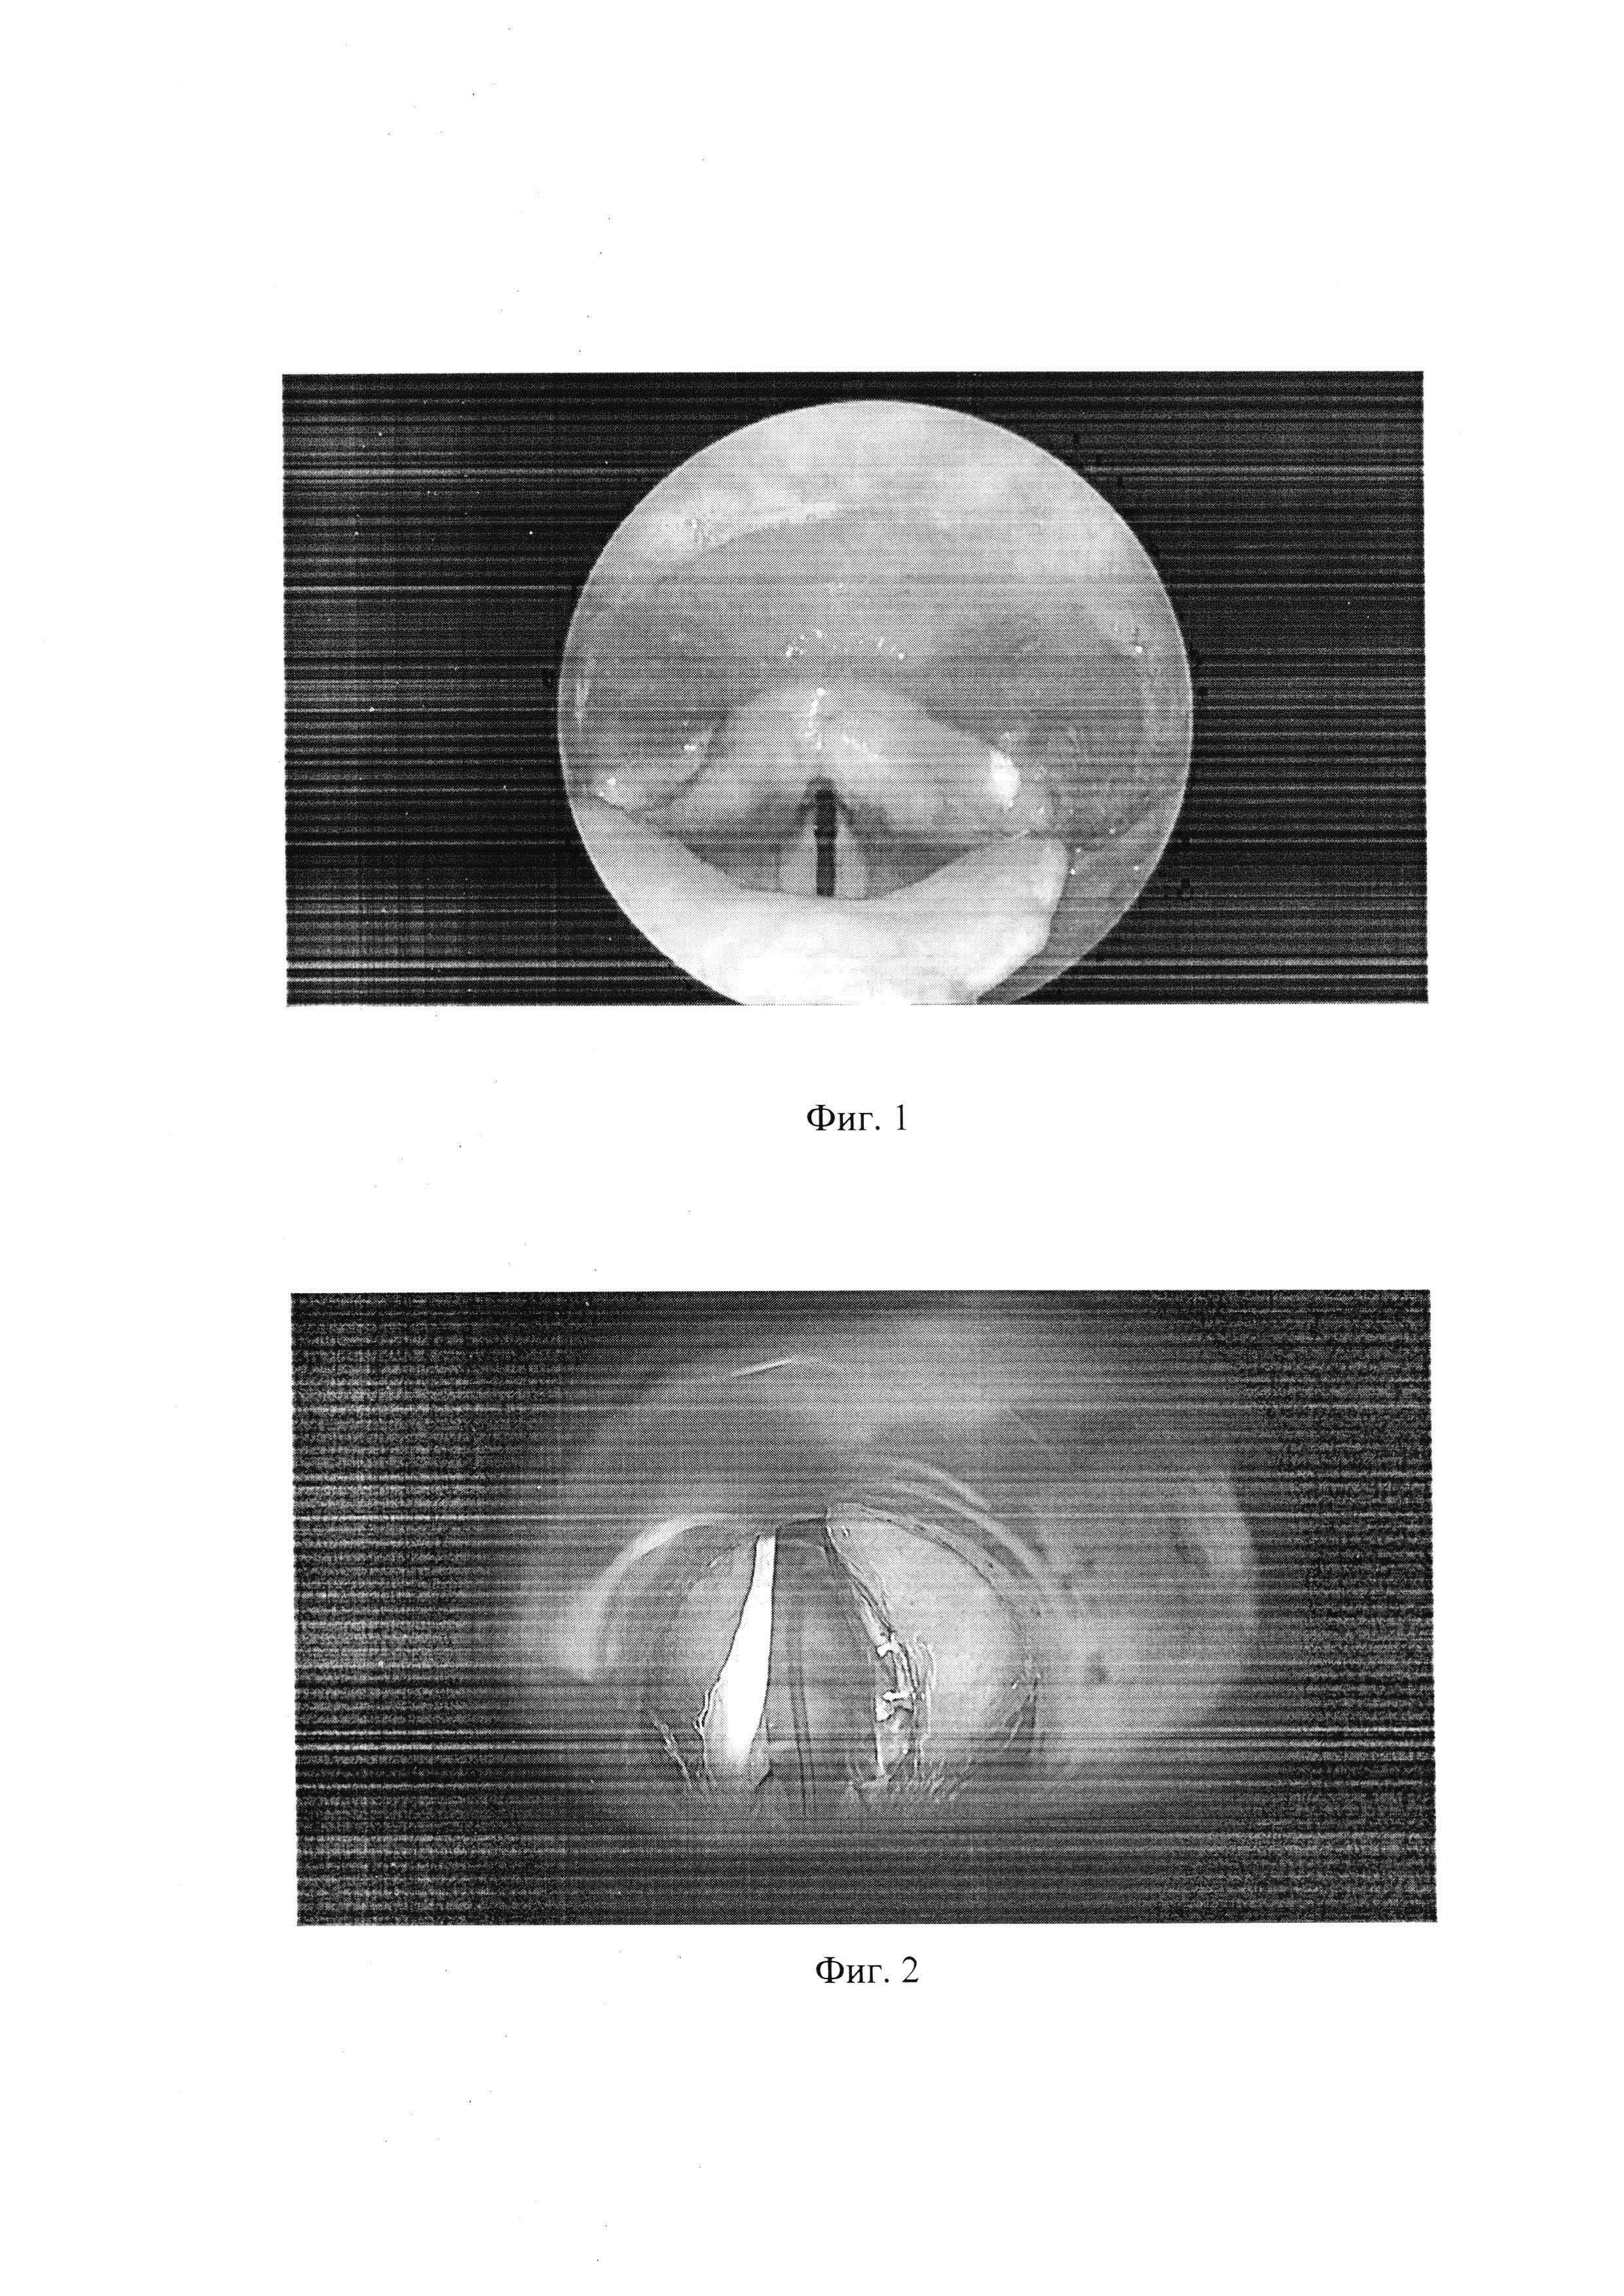

Область техники Изобретение относится к медицине, в частности к оториноларингологии, и может быть использовано для лечения срединных параличей гортани с улучшением дыхания и сохранением удовлетворительного качества голоса. Уровень техники Двусторонний паралич гортани (ДПГ) - патологическое состояние, сопровождающееся стойким и необратимым нарушением подвижности гортани в результате нарушения двигательной иннервации, обусловленной поражением блуждающего нерва, чаще всего его ветви - возвратного нерва. Данная патология имеет большую социальную значимость в связи с тем, что около 80-90% больных нейрогенными стенозами гортани составляют лица трудоспособного возраста. При этом женщины составляют 86% таких пациентов. В современной ларингологии описано множество методик хирургического лечения ДПГ, которые сводятся к двум основным методам: динамические и статические. Статические методы направлены на расширение просвета голосовой щели, к ним относятся: латерофиксация, хордэктомия, хордотомия, аритеноидэктомия, аритеноидхордэктомия. Вышеперечисленные хирургические вмешательства осуществляются посредством холодного инструментария, лазеров (контактные лазеры, СО2 -лазер), коблатора, электрокоагулятора. Классификация статических хирургических методов лечения ДПГ изложена в работе P.Lavertu et H.Tucker, выделены 2 основных хирургических доступа: 1. Трансцервикальный доступ (доступ через наружный разрез кожи и тканей шеи): а) эндоларингеальный доступ - наружный доступ через срединную тиреотомию, б) экстраларингеальный доступ - подход к гортани со стороны шеи без вскрытия ее просвета, разрез кожи и мягких тканей в области заднего края пластины щитовидного хряща. 2. Эндоскопический доступ к внутренним структурам гортани осуществляется через естественные дыхательные пути (аритеноидэктомия, хордэктомия, задняя хордэктомия, временная и окончательная латерализация голосовой складки). Отечественная классификация Ф.А. Тышко (1973) выделяет эндоскопический, эндоларингеальный и экстраларингеальный доступы. Динамические операции (нейропластика), направленные на восстановление иннервации гортанных мышц, не получили широкого применения ввиду сложной и длительной техники операций без точно прогнозируемого положительного результата. Исходом таких операций часто было нарушение двигательной активности гортанных мышц. Электростимуляция мышц гортани с помощью нейропротезов с целью восстановления подвижности голосовых складок является эффективным методом выбора лечения двустороннего паралича гортани в перспективе, но пока эта методика находится на стадии разработки. Известен способ лечения двусторонних нейрогенных стенозов гортани паралитической этиологии (Патент 2440792, опубл. 27.01.2012), который включает латерально-вертикальное перемещение черпалобидного хряща и отведение голосовой складки, при котором выявляют и отсекают боковую перстне-черпаловидную и наружную щито-черпаловидную мышцы, резецируют 2/3 мышечного отростка черпаловидного хряща, проводят две лигатуры через тело черпаловидного хряща и голосовой отросток, выводят их на наружную поверхность пластинки щитовидного хряща, отводят черпаловидный хрящ с голосовой складкой латеро-вертикально, связывают лигатуры между собой, проводят третью лигатуру через тело черпаловидного хряща, фиксируют ее через верхний рожок щитовидного хряща, связывают все лигатуры между собой на наружной поверхности пластинки щитовидного хряща. Недостатками данного способа являются: 1) экстраларингеальный доступ с резекцией хрящей гортани сопряжен с риском инфицирования и хондроперихондрита гортани, 2) метод не выполним при отсутствии трахеостомы у больного из-за риска респираторных нарушений в раннем послеоперационном периоде, 3) существует риск развития нарушения разделительной функции гортани с развитием аспирационно синдрома, 4) имеется риск ослабления или прорезывания шва, что может отразиться на неблагоприятном результате в послеоперационном периоде, 5) разобщение голосовых складок на всем протяжении создает более выраженный риск неудовлетворительного голосоведения после операции. Также известен способ эндоэкстраларингеального хирургического лечения паралитических стенозов гортани (патент 2525220, опубл. 10.08.2014), который заключается в том, что после отслаивания слизистого лоскута выполняют иссечение средней и задней трети голосовой складки, голосовой мышцы, голосового отростка черпаловидного хряща и части эластического конуса с одномоментной экстраларингеальной фиксацией лигатурой, проведенной через инъекционные иглы, операционной зоны к щитовидному хрящу оперируемой стороны после укутывания ее слизистым лоскутом. Недостатками данного способа являются: 1) эндоэкстраларингеальная латерофиксация голосовой складки, как правило, имеет временный результат в связи с прорезыванием нитью голосовой складки, 2) применение холодного инструментария вызывает интраоперационные сложности визуализиции хирургом структур гортани в маленьком хирургическом поле, 3) невозможность одномоментной коагуляции холодным инструментарием, что сопряжено с высоким риском кровотечения, 4) в связи с высокой травматичностью холодного инструментария послеоперационный период протекает с реактивными явлениями в гортани, 5) эндоэкстраларингеальный шов может способствовать развитию грануляций и воспалению мягких тканей гортани. Наиболее близким к предлагаемому нами способу является способ хирургического лечения параличей гортани с применением контактного полупроводникового лазера (Долгов О.И. Эндоскопическое хирургическое лечение и реабилитация больных с паралитическими стенозами гортани: дис… канд. мед. наук. - М., 2015. - 137 с.), заключающийся в проведении лазерной парциальной хордаритеноидэктомии (пХАЭ) с расширенным вариантом лазерных резекций, а именно иссечение более 1/3 голосовой складки; дополнительное поперечное рассечение щиточерпаловидной мышцы; распространение зоны резекции на вестибулярную складку; рассечение рубцовых изменений в области голосовых складок. Оперативные вмешательства осуществлялись под общим наркозом, с применением хирургической лазерной установки «АКТУС-15» (фирма «Полупроводниковые приборы», Россия), в контактном режиме, мощностью 7-8 Вт производился разрез слизистой оболочки в области задней трети голосовой складки. Далее разрез направлялся латерально, огибая голосовой отросток черпаловидного хряща, затем послойно разрез углублялся, при достижении достаточной глубины резецируемый фрагмент фиксировался щипцами и отсекался. Преимущества метода: восстановление дыхательной функции, сохранение голосовой функции удовлетворительного качества. Недостатком метода является использование контактного лазера в условиях небольшого операционного поля и, следовательно, недостаточной визуализации операционной раны, что может помешать точности исполнения действий в ходе операции. Задачей настоящего изобретения является разработка способа проведения задней хордотомии при двусторонних параличах гортани, в результате осуществления которого происходит восстановление дыхательной функции с максимальным сохранением фонаторной функции. Для решения данной задачи мы предлагаем способ хирургического лечения двустороннего паралича гортани, заключающийся в том, что СО2-лазером мощностью 7 Вт в непрерывном режиме проводят продольный разрез слизистой верхней поверхности голосовой складки в области ее задней трети, отступя на 2-3 мм от края, затем выполняют продольный разрез слизистой оболочки задней трети вестибулярной складки, отступя 2-3 мм от ее края, с переходом на слизистую оболочку, выстилающую морганиев желудочек, и находящуюся между двумя произведенными разрезами, удаляют, после этого лазером иссекают заднюю треть голосовой мышцы с сохранением слизистой оболочки на нижней поверхности голосовой связки, далее резецируют голосовой отросток черпаловидного хряща, сохраненный лоскут слизистой оболочки голосовой складки с отсеченным голосовым отростком черпаловидного хряща подшивают к вестибулярной складке в области проведенного разреза. Технический результат предлагаемого способа заключается в том, что проведение иссечения задней трети мышцы голосовой складки обеспечивает увеличение просвета гортани, а сохранение лоскута слизистой нижней поверхности голосовой связки и подшивание его к вестибулярной складке обеспечивает закрытие раневой поверхности, позволяет снизить возможность формирования гранулем и рубцового стеноза в зоне послеоперационной раны, что является профилактической мерой возможных осложнений. Хирургическое вмешательство осуществляется с помощью дистанционного (бесконтактного) воздействия СО2-лазером мощностью 7 Вт, который обеспечивает хирургу точную работу, малую травматичность и бескровность, зона коагуляционного некроза небольшая, в результате чего происходит быстрое заживление ран. Сохранение слизистого лоскута голосовой складки, передне-средних отделов голосовых складок позволяет сохранить хорошее качество голоса, а увеличение просвета голосовой щели за счет резекции задних отделов голосовой складки способствует восстановлению дыхательной функции. Сущность изобретения Способ осуществляется следующим образом: под общей анестезией (проводилась тотальная внутривенная анестезия (пропофол, фентанил) с применением мышечных релаксантов (нимбекс)) эндотрахеально проводят прямую опорную ларингоскопию. В просвет гортани вводится защита на интубационную трубку (влажная марлевая салфетка), а затем интубационная трубка, через которую вводят световод СО2-лазера. СО2-лазером (фирма Lumenis, с насадкой AcuBlade), мощностью 7 Вт, в непрерывном режиме проводится продольный разрез слизистой верхней поверхности голосовой складки в области ее задней трети, на расстоянии 2-3 мм от ее края. Затем проводится продольный разрез слизистой оболочки задней трети вестибулярной складки на расстоянии 2-3 мм от ее края. Расстояние от края складки до разреза определяется с учетом физиологических особенностей конкретного пациента. После этого слизистая оболочка, выстилающая морганиев желудочек, и находящаяся между двумя произведенными разрезами, удаляется. После этого лазером иссекается задняя треть голосовой мышцы с сохранением слизистой оболочки на нижней поверхности голосовой связки. Затем резецируется голосовой отросток черпаловидного хряща. Сохраненный лоскут слизистой оболочки голосовой складки с отсеченным голосовым отростком черпаловидного хряща подшивается к вестибулярной складке в области проведенного разреза рассасывающейся нитью, например Vicryl № 7. В послеоперационном периоде назначают антибиотикотерапию, гормонотерапию, ингаляционную терапию. Краткое описание поясняющих материалов. Фиг. 1. К примеру 1. Ларингоскопическая картина до операции (голосовые складки в парамедианном положении, неподвижные при фонации, голосовая щель сужена). Фиг. 2. К примеру 1. Интраоперационная ларингоскопическая картина (в области послеоперационной раны швы, голосовая щель расширена в задних отделах). Фиг. 3. К примеру 1. Ларингоскопическая картина через 2 месяца (голосовые складки белые, неподвижные при фонации, голосовая щель широкая). Осуществление изобретения Пример 1. Больная Б., 55 лет, поступила в НКЦО 10.09.18 с жалобами на одышку, чувство нехватки воздуха при минимальной физической нагрузке. Из анамнеза: в 2015 г по поводу многоузлового зоба щитовидной железы выполнена струмэктомия. В настоящее время госпитализирована для хирургического лечения. При эндоскопическом осмотре определяется двусторонний абдукционный паралич гортани (фиг. 1), просвет сужен до 3 мм, складки при фонации неподвижны. 11.09.12 больной выполнена операция: Задняя хордотомия левой голосовой складки СО2-лазером с формированием лоскута, согласно заявленному изобретению (фиг. 2). Под общей анестезией установлен подвесной ларингоскоп, далее СО2-лазером мощностью 7 Вт, в непрерывном режиме произвели продольный разрез слизистой верхней поверхности голосовой складки в области ее задней трети на расстоянии 2 мм от края. Затем произвели продольный разрез слизистой оболочки задней трети вестибулярной складки на расстоянии 3 мм от края. После этого слизистую оболочку, выстилающую морганиев желудочек, и находящуюся между двумя произведенными разрезами, удаляли. После этого лазером иссекали заднюю треть голосовой мышцы с сохранением слизистой оболочки на нижней поверхности голосовой связки, резецировали голосовой отросток черпаловидного хряща. Сохраненный лоскут слизистой оболочки голосовой складки с отсеченным голосовым отростком черпаловидного хряща подшивали к вестибулярной складке в области проведенного разреза рассасывающейся нитью (vicryl № 7). В послеоперационном периоде проводилась антибиотикотерапия (цефтриаксон 1.0 г х2 раза в день в/в 1-3 дня), гормонотерапия, ингаляционная терапия через небулайзер (суспензия гидрокортизона 0.5 мл + раствор диоксидина 0.5 мл + физиологический раствор 2.0 мл). Послеоперационный период протекал без осложнений. При контрольном осмотре: состояние больной удовлетворительное. Ларингоскопичекая картина: увеличение просвета голосовой щели в задних отделах, дыхание через естественные дыхательные пути свободное, голос звучный (фиг. 3). Под нашим наблюдением с 2014 по 2018 находилось 143 пациента с диагнозом: двусторонний периферический паралич гортани. Пациентам проводилось хирургическое лечение заявленным способом. В послеоперационном периоде осложнений не наблюдалось, отмечалось хорошее качество голоса, увеличение просвета голосовой щели, восстановление дыхательной функции.